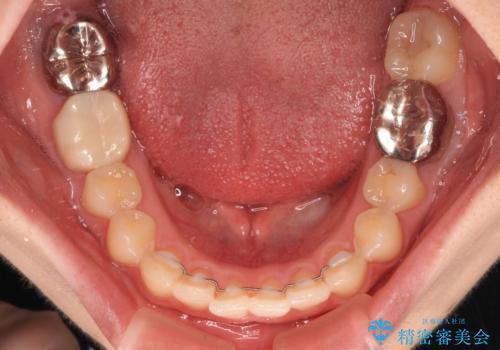

1年半程度で終了するのではないかと予想しましたが、途中1年以上の来院がなく、トータルで3年の時間がかかってしまいました。

前歯のデコボコはより改善することが望ましい状態でしたが、患者様の希望により終了することとなりました。